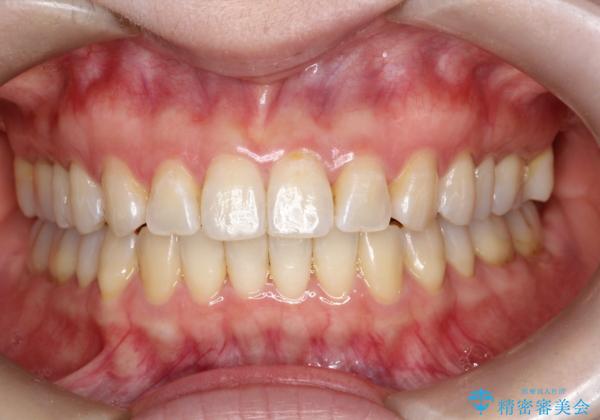

- 前歯の凸凹を主訴に来院されました。

インビザライン にて治療を行い、歯並びが綺麗になったと満足していただきました。

前歯のガタガタの量が多かったため、IPR(歯のサイズを小さくするための処置)を行なって治療しました。